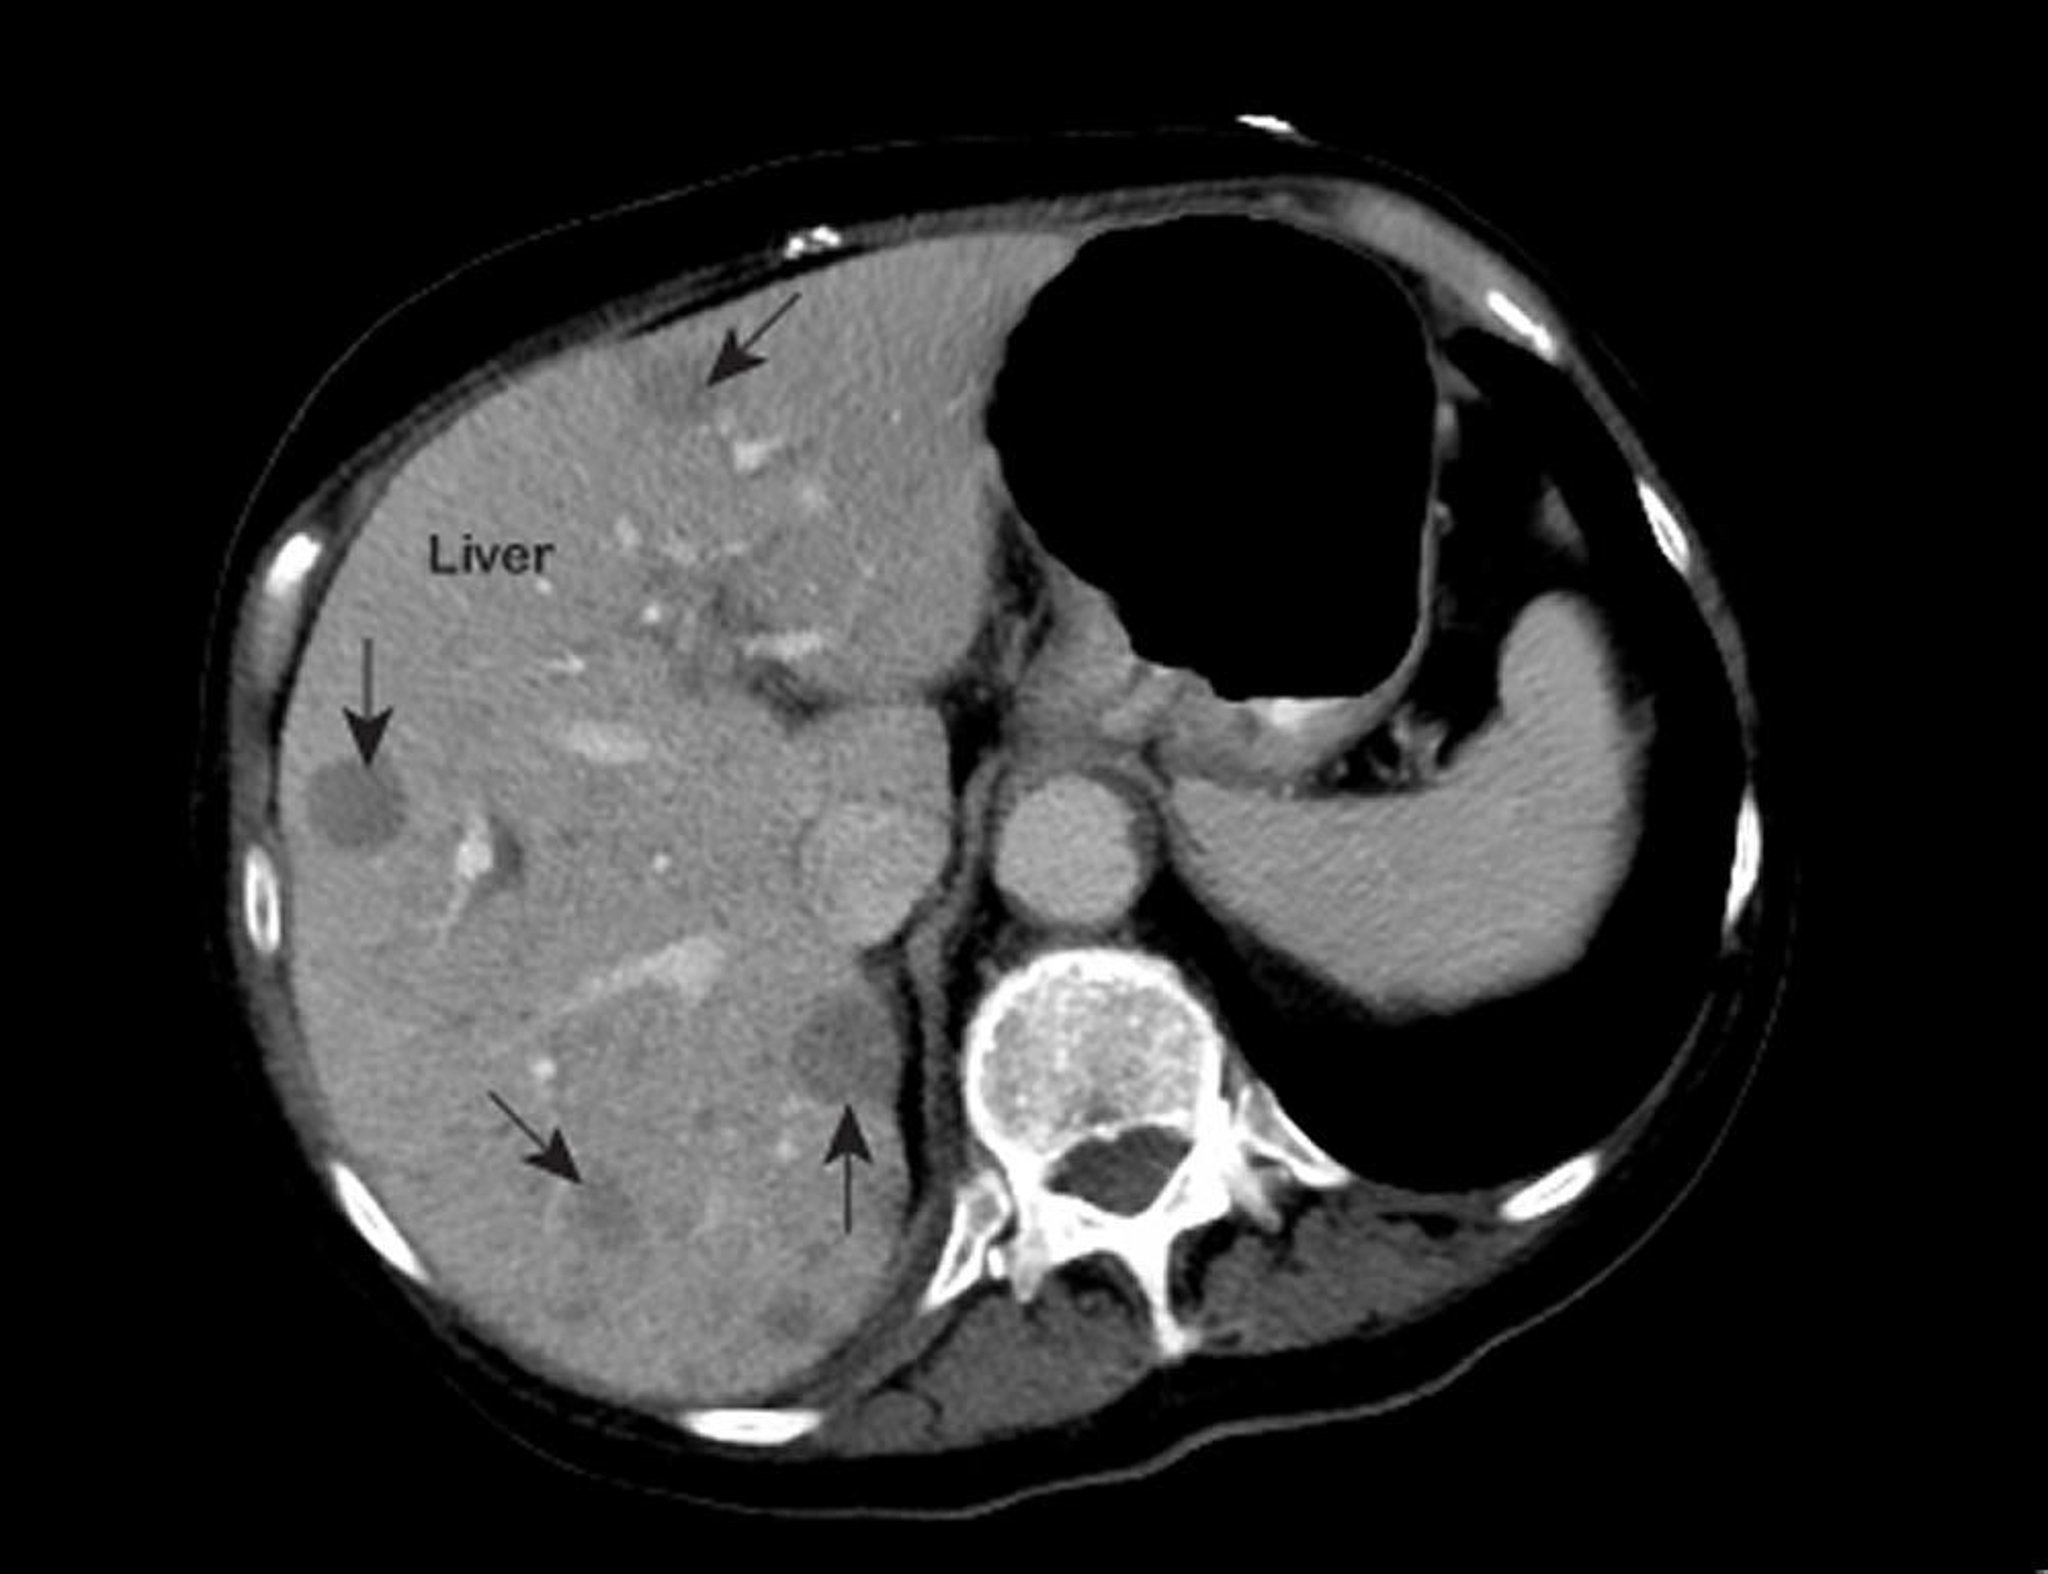

Если врачи подозревают наличие рака печени, для оценки того, насколько хорошо печень функционирует, проводят печеночные пробы, которые представляют собой простые анализы крови. Как и в случае многих других нарушений, результаты могут отклоняться от нормы. Таким образом, этот результат не может служить подтверждением диагноза. Обычно полезную информацию дает ультразвуковое исследование, но компьютерная томография (КТ) и магнитно-резонансная томография (МРТ) печени при обнаружении рака, как правило, обладают более высокой точностью. Перед КТ или МРТ внутривенно вводится контрастное вещество. Контрастное вещество помогает лучше видеть отклонения от нормы, если они есть (см. Визуализирующие обследования печени и желчного пузыря). Тем не менее, визуализирующие обследования не всегда могут обнаружить маленькие опухоли или отличить рак от цирроза или других патологий.